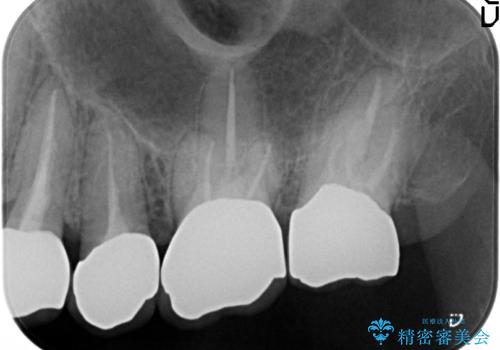

クラウンの除去・虫歯の除去、根管治療を行ったのち、上顎は強い咬合力に対し破折抵抗性のある咬合面をメタルにしたメタルボンドによる補綴を計画します。

今回は破れにくいセラミック治療としてメタルボンドを選択しました。

外側からは金属色の見えない設計となっています。